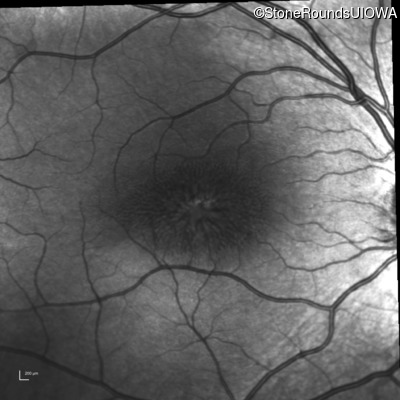

This 6 year old boy first experienced difficulty reading and seeing the blackboard at age 5.

| Age at visit: 6 years |